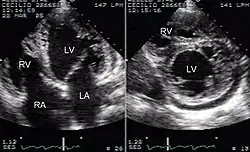

Niescalony mięsień lewej komory (ang. noncompaction cardiomyopathy, left ventricular non-compaction, LVNC) – heterogenna etiologicznie, uwarunkowana genetycznie nieprawidłowość rozwojowa mięśnia lewej komory serca, zaliczana obecnie według klasyfikacji ESC do kardiomiopatii niesklasyfikowanych, a wedle klasyfikacji AHA do kardiomiopatii pierwotnych genetycznych[2], charakteryzująca się wzmożonym beleczkowaniem lewej komory i pogłębieniem zatok międzybeleczkowych. Istnieją rozbieżne opinie co do charakteru LVNC; część badaczy jest zdania, że stanowi odrębną kardiomiopatię, podczas gdy inni widzą w niej cechę wspólną wielu fenotypowo odmiennych postaci kardiomiopatii.